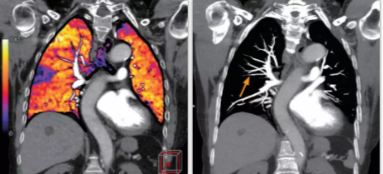

相比傳統(tǒng)成像方式,肺部柔性減影技術(shù)通過人工智能,對平掃數(shù)據(jù)和CT肺動脈血管掃描數(shù)據(jù)進行智能比對,解碼并識別各個器官(肺、氣管、肺動脈、肺靜脈、主動脈等)的空間位置,并在三維空間中進行體素級的柔性配準,從而極大提升了不同序列數(shù)據(jù)的空間位置的一致性。通過肺部柔性減影技術(shù)可得到肺強化碘圖,可以顯示出傳統(tǒng)CTPA圖像看不到的小栓塞病變,提高了栓塞檢出率,其結(jié)果甚至可與SPECT吻合。

肺智能柔性減影成像功能發(fā)現(xiàn)亞段肺栓塞